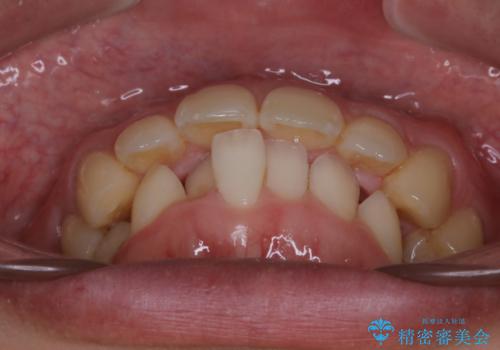

がたつき、口ゴボ(出っ歯)、真ん中のずれを抜歯矯正治療で治す。ワイヤー矯正治療

- 口元の突出感とがたつきを気にして来院されました。

突出感とがたつきの改善を行うために大きなスペースが必要であったため、親知らず以外の歯を4本歯を抜歯する計画を立てました。

移動量が大きいこと、また、患者さんの生活習慣的にマウスピース装着が難しそうとの理由から

ワイヤー表側矯正装置で治療を行うことになりました。